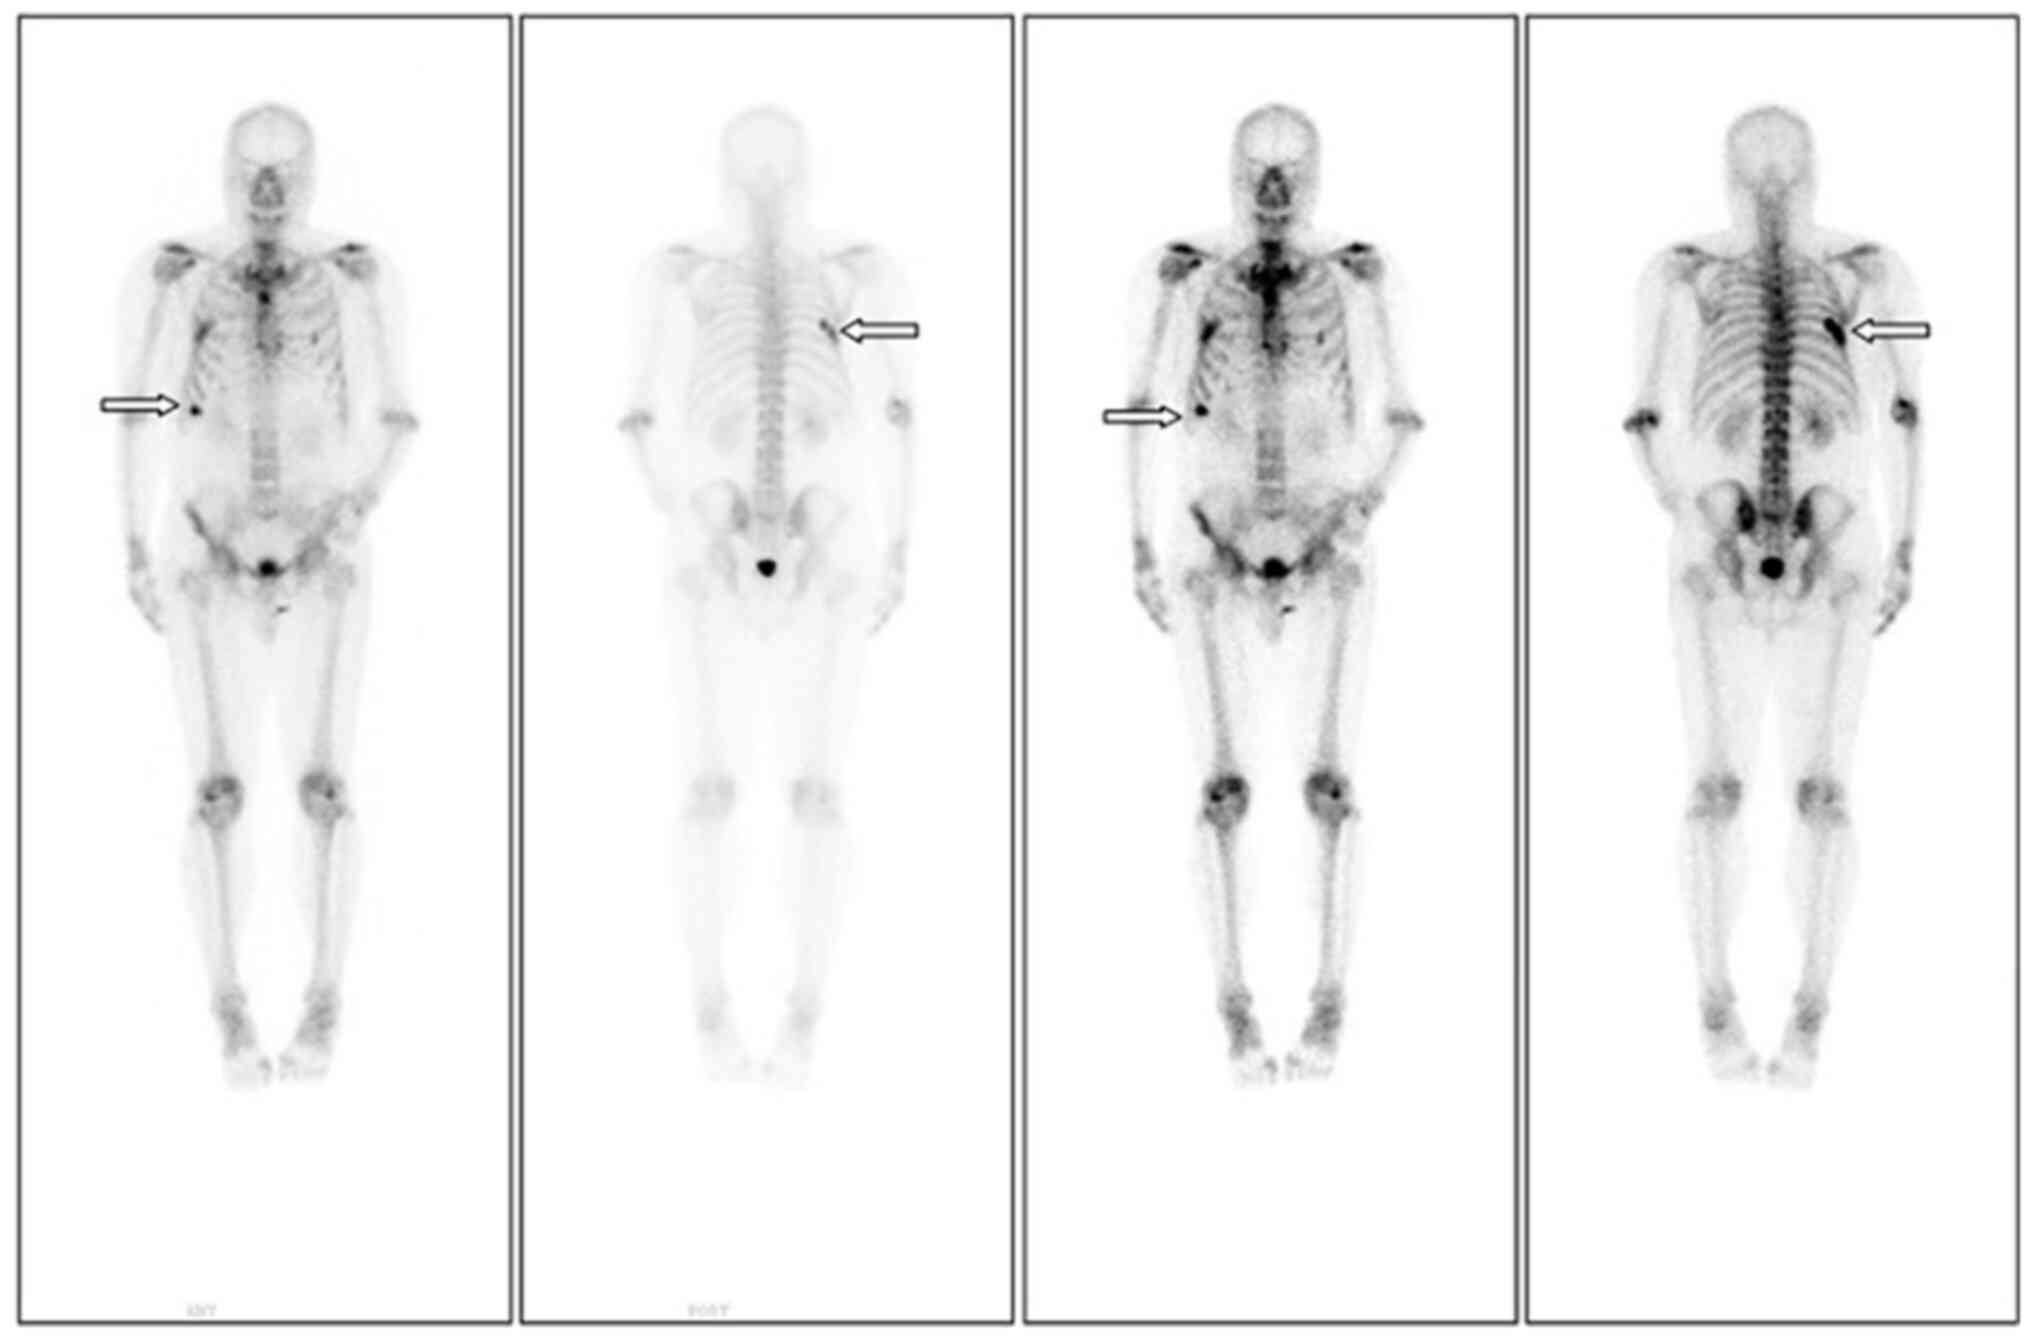

The patient is a 65-year-old male who was diagnosed with rectal cancer in October 2013 at Southwest Hospital (Chongqing, China). The patient underwent laparoscopic abdominoperineal resection (Miles procedure) for rectal cancer at Chongqing Southwest Hospital. It was not possible to obtain postoperative pathological images from the hospital. The postoperative pathological result was poorly differentiated adenocarcinoma (stage T3N1M0) with a moderate risk of recurrence. Following surgery, the patient received standard chemotherapy according to the FOLFOX regimen (oxaliplatin, calcium folinate and 5-fluorouracil). The patient underwent regular follow-ups every year through abdominal computerized tomography (CT), colonoscopy and assessment of serum carcinoembryonic antigen (CEA) levels after surgery. No tumor recurrence or metastasis was observed during the 6-year follow-up period. In addition, in October 2019, the patient visited our hospital (Affiliated Hospital of Zunyi Medical University, Zunyi, China) due to ‘right-sided back pain’. Chest CT revealed bone destruction of the seventh posterior rib on the right side. An emission CT (ECT) was conducted to further evaluate the overall condition. ECT showed increased metabolic activity in the right seventh rib, indicating the possibility of bone metastasis (Fig. 1). Abdominal CT and colonoscopy revealed no local tumor recurrence or peritoneal metastasis, and CEA levels were within the normal range. Based on his medical history, the patient was considered to have developed postoperative bone metastasis from rectal cancer. The patient then sought medical care at Southwest Hospital (Chongqing, China). Spinal magnetic resonance imaging (MRI) was performed at Southwest Hospital, revealing multiple vertebral body lesions involving the thoracic, lumbar and sacral regions, as well as abnormal enhancement in the appendages and bilateral iliac bones. Positron emission tomography (PET)/CT has high specificity and sensitivity; therefore, the patient underwent a PET/CT examination at Southwest Hospital. The sternum, multiple vertebrae and sixth/seventh rib on the right side showed bone destruction and slightly increased glucose metabolism (images not available, as only retrievable by the patient). Clinicians at that hospital also assumed that the patient had developed bone metastasis following rectal cancer treatment. They considered that the previous FOLFOX chemotherapy regimen was effective and its use could be continued.

Figure 1.

First emission computed tomography examination after the onset of bone pain. The increase in bone metabolism in the right 7th posterior rib (arrows) suggest a multiple myeloma lesion. The increase in bone metabolism in the right eighth anterior rib (arrows) suggests a benign lesion.

After clarifying the condition, the patient returned to our hospital for chemotherapy according to the FOLFOX regimen. After six rounds of chemotherapy, the patient's bone pain symptoms did not improve significantly. Follow-up ECT revealed the emergence of a new lesion on the left tenth rib, compared with the pre-chemotherapy image (Fig. 2). Owing to significant bone pain, orthopedic experts recommended using zoledronic acid to inhibit osteoclasts. Although the patient experienced temporary pain relief with this treatment, the pain returned and worsened over time. Subsequently, the patient's treatment was changed to dinozumab and he received eight courses of treatment. However, the patient's bone pain still did not show any significant improvement. Reexamination with ECT (Fig. 3) indicated active bone metabolism in the right seventh posterior rib, left tenth posterior ribs, upper sternum and first lumbar spine.

Figure 2.

After six cycles of chemotherapy with the FOLFOX (oxaliplatin, calcium folinate and 5-fluorouracil) regimen, an ECT examination was performed. Compared with the previous ECT results, an additional left tenth rib lesion was observed, and bone metabolism was increased in the anterior aspect of the left fourth rib, right sixth rib and right eighth rib, suggesting benign lesions (arrows). ECT, emission computed tomography.

Figure 3.

One year after the onset of bone pain, ECT was performed, indicating active bone metabolism in the right seventh rib (fourth column arrow), upper sternum (third column arrow) and first lumbar spine (second column arrow). Compared with the previous ECT results, new lesions were identified. However, compared with the positron emission tomography/computed tomography results, no new lesions were found, though the local lesions had progressed. ECT, emission computed tomography.